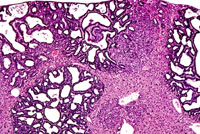

Hepatocellular adenoma and bile duct carcinoma in a 4-week-old transgenic mouse.

A proliferative cystic biliary lesion, a solid basophilic adenoma, and a bile duct adenoma in a 4-week-old transgenic mouse.

Juxtaposition of a bile duct adenocarcinoma and a hepatocellular adenoma in a 4-week-old transgenic mouse.

Cholangiocarcinoma next to a more adenomatous lesion with hepatocyte cytological features in a 4-week-old transgenic mouse.